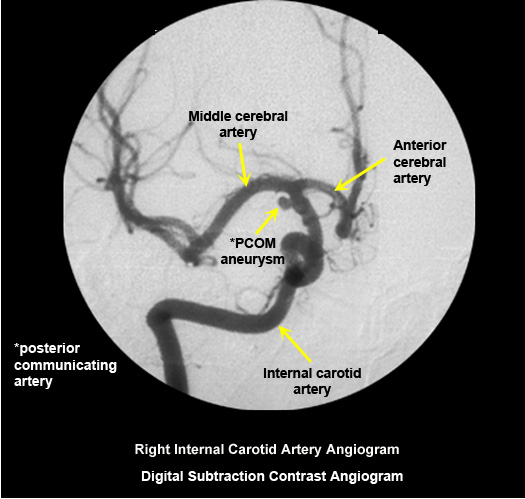

Nature of vascular abnormality? Options to investigate?

- Is the primary abnormality in extracranial arteries or intracranial arteries?

- Doppler US is the least expensive study to evaluate carotid bifurcations. MR angiogram and CT angiogram are non-invasive studies to investigate extra and intracranial arteries. Digital subtraction intra-arterial contrast angiogram (DSA) is invasive and definitive. If interventional therapy is contemplated, such as retrieval of clot from major arteries one needs to do dedicated invasive digital subtraction contrast angiogram.

Normal digital subtraction contrast angiogram

Arterial puncture required.

Selective intra arterial contrast injection into right internal carotid artery. |